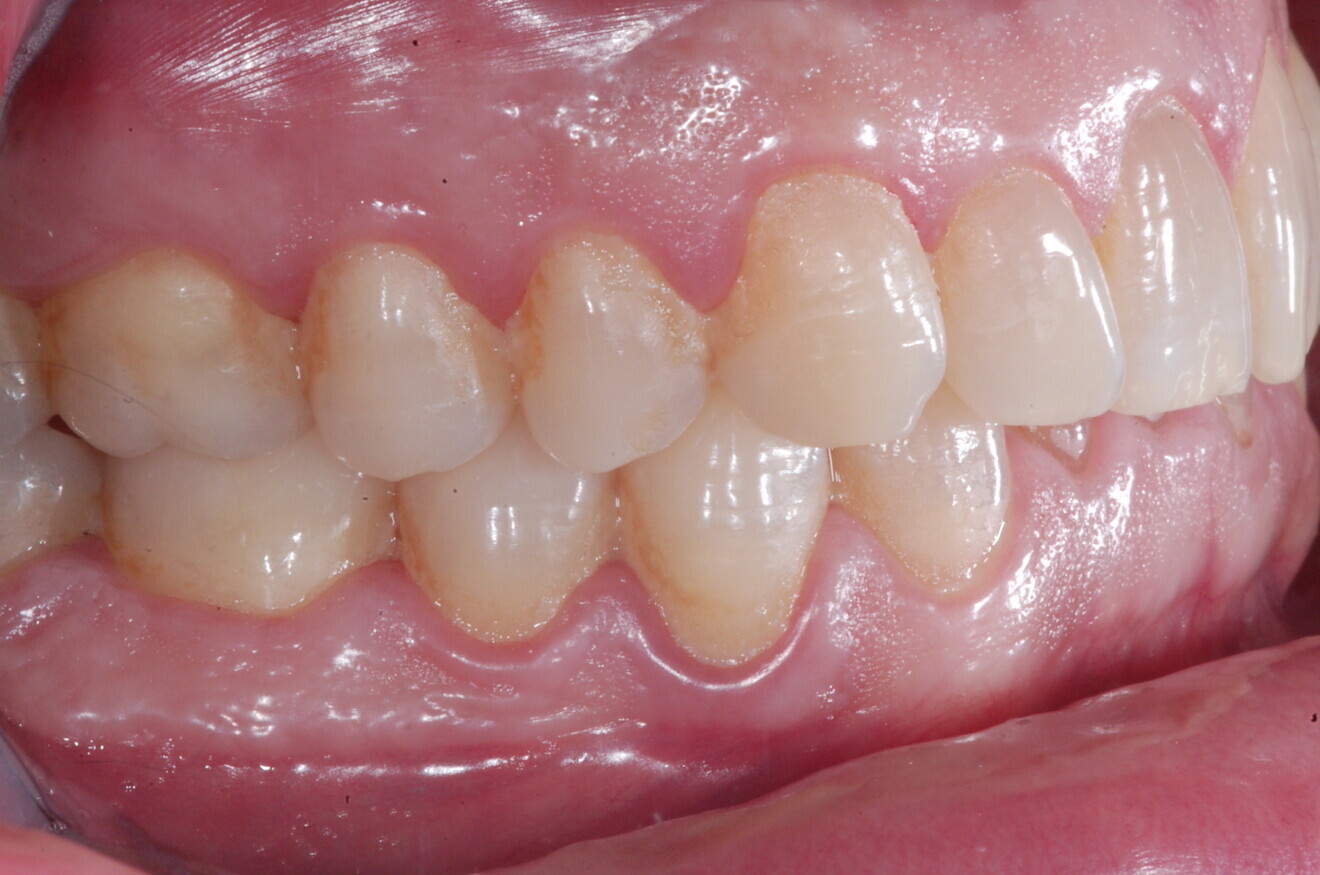

Fig. 13

Fig. 14

Fig. 15

Fig. 16

Fig. 17

Fig. 18

A 37-year-old male patient presented with the chief need for re establishing anterior alignment in both arches. Facial analysis showed a short face with a flat profile but proper chin projection (Figs. 9–12), and clinical examination revealed a skeletal Class I (ANB = 0.89°) and dental Class I malocclusion with severe deep bite (almost 100%), a deep curve of Spee, normal maxillary central incisor torque (Ui–FH = 110°), mild maxillary crowding and moderate mandibular crowding (Figs. 13–18). The deep bite components were represented in this patient by the severe skeletal condition of hypo divergent pattern (FMA = 14.24°) with normal maxillary and mandibular incisor inclination and decreased gonial angle (110.46°). Analysis of the cephalometric radiograph indicated a reduced lower anterior facial height, combined with a hypo-divergent pattern (Fig. 19). The only treatment option suggested was orthodontic treatment with aligners for deep bite correction with all the features described (bite ramps, pressure area, 3D curve of Spee levelling, Class II elastics and heavy occlusal contacts).